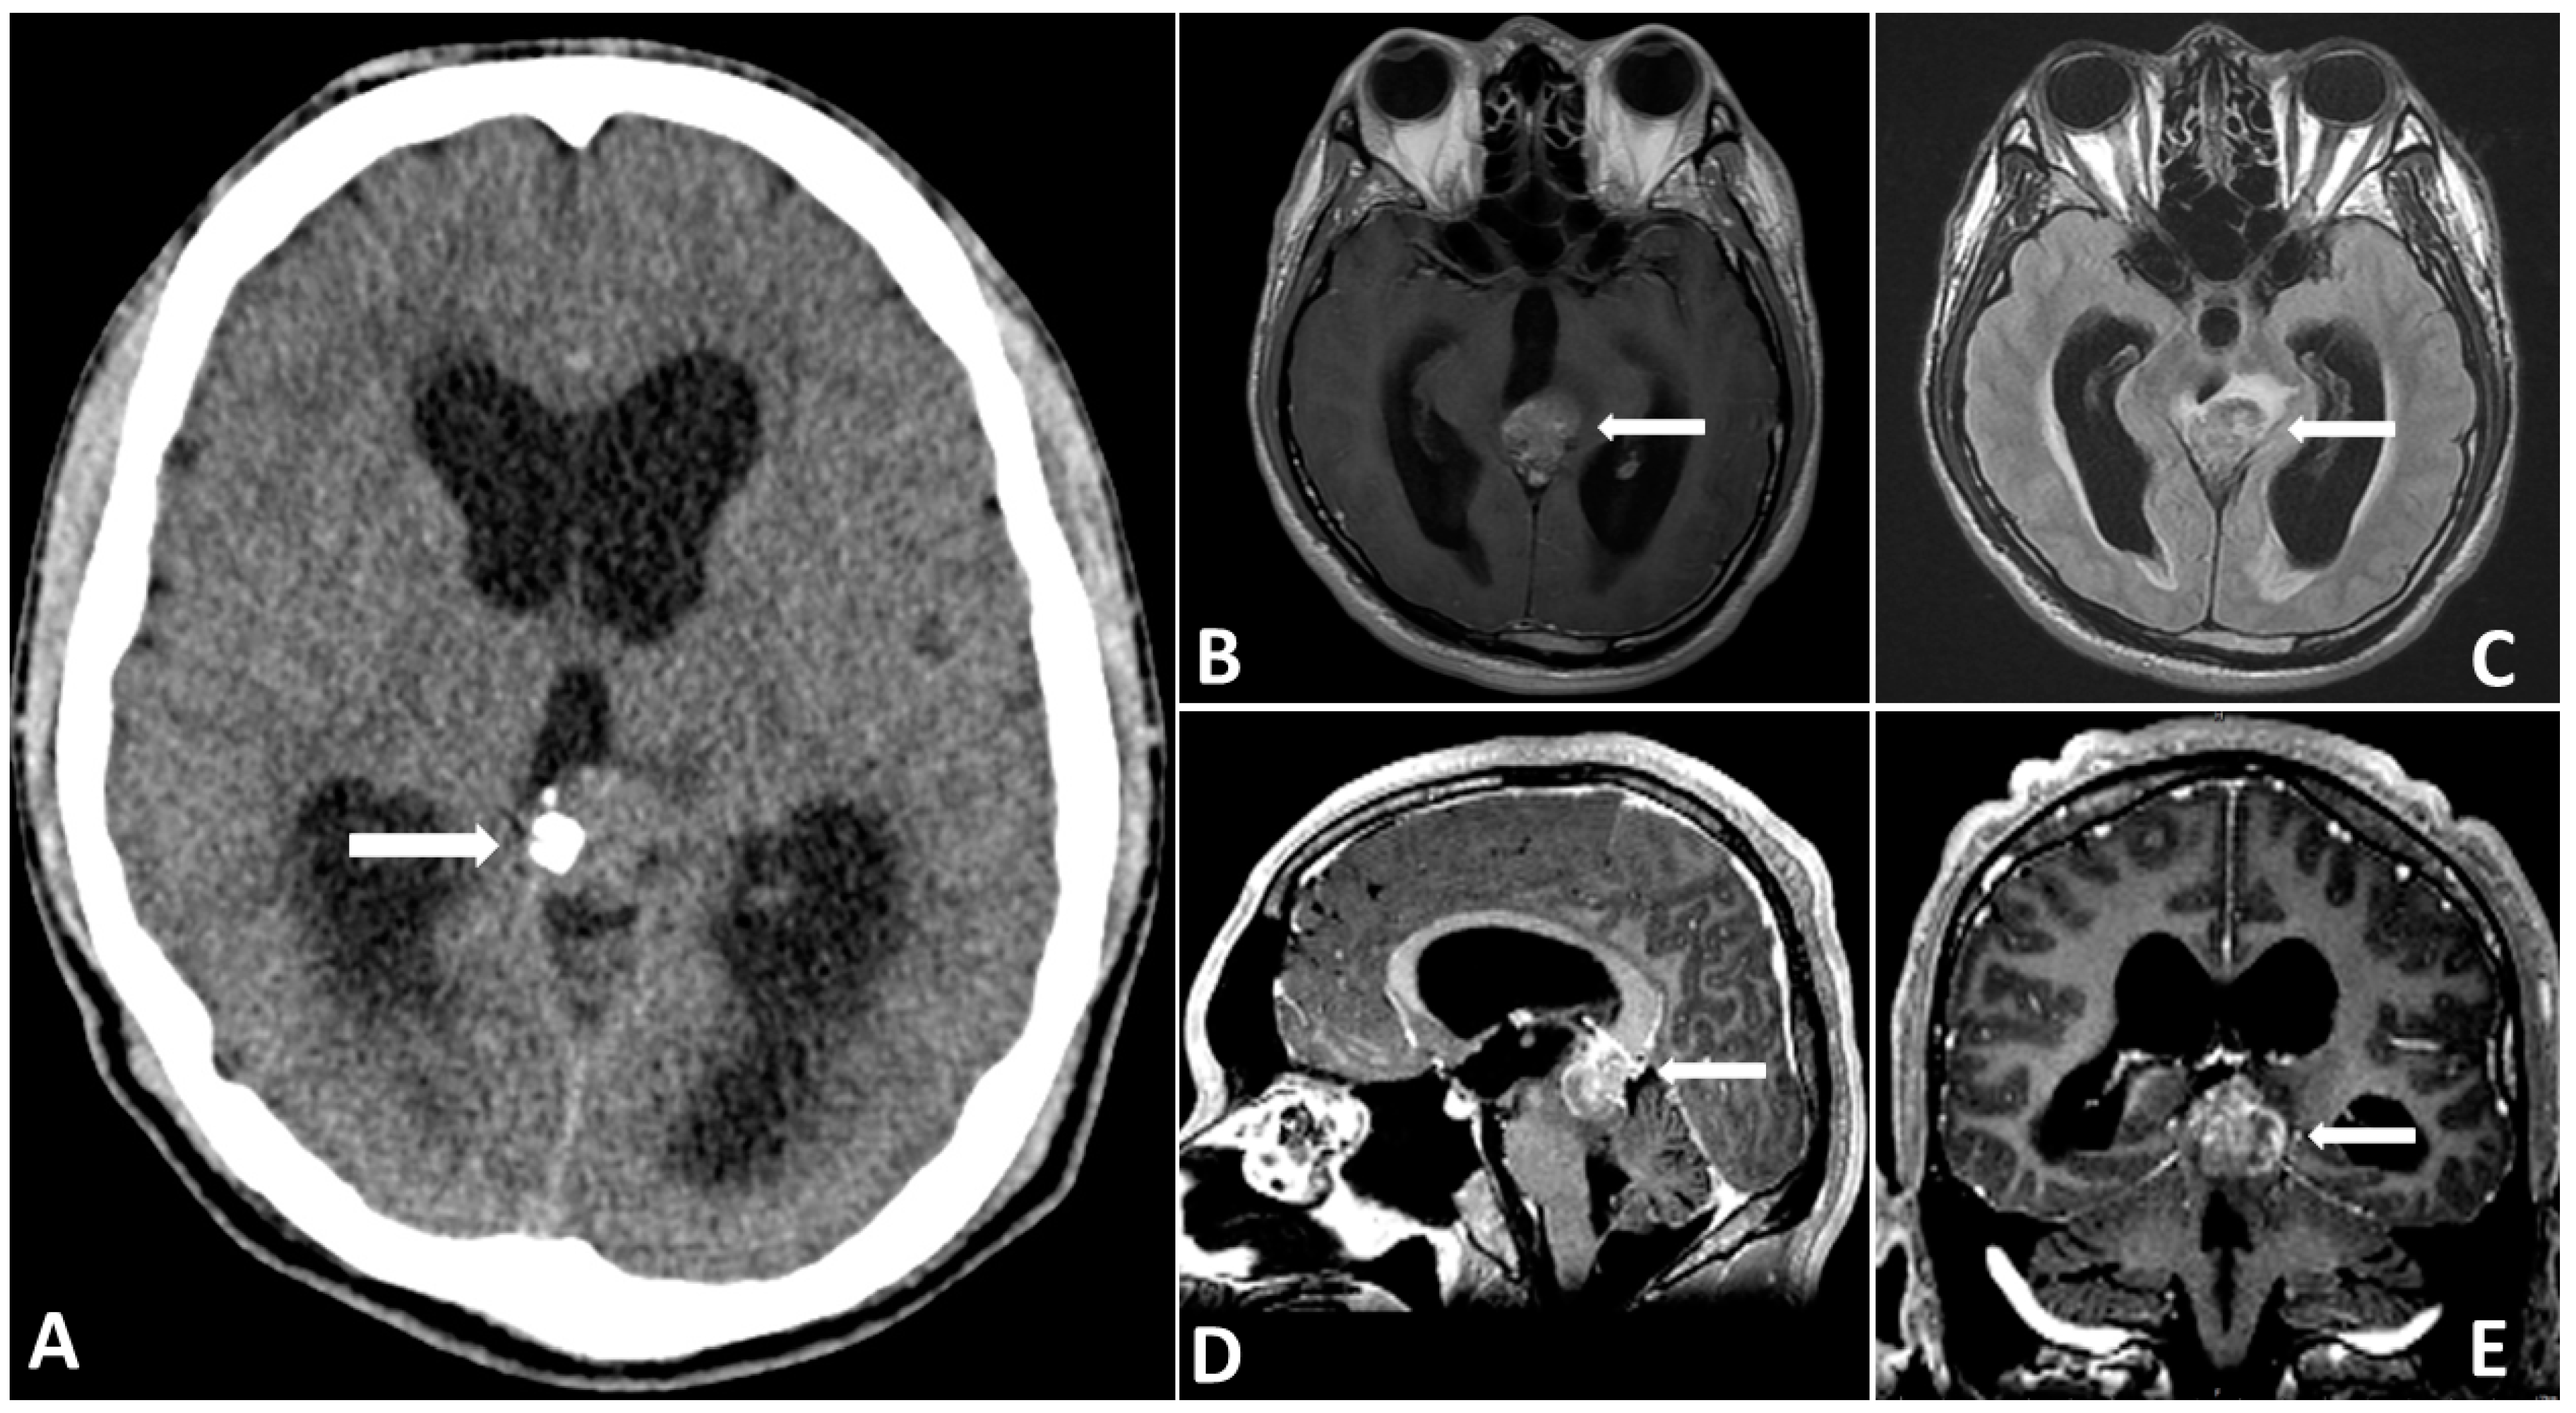

Figure 1.

Preoperative CT (A) showing a partially calcified mass in the pineal region causing hydrocephalus. Preoperative MRI showing that the (B) tumor mass is hyperintense on T2-FLAIR images. (C–E) Gadolinium-enhanced MRI, revealing a large pineal region tumor with heterogenous contrast enhancement.